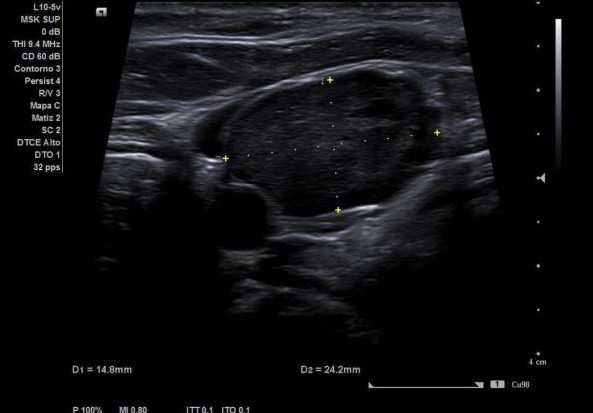

Dada la clínica y la exploración física, se decide realizar ecografía clínica en el Centro de Salud, con los siguientes resultados:

Este caso, destaca la importancia de la ecografía en la evaluación inicial de las tumoraciones cervicales en Atención Primaria. La identificación temprana de lesiones con características ecográficas de malignidad, como los procesos linfoproliferativos (entre ellos el linfoma), es clave para un tratamiento oportuno y mejora del pronóstico.